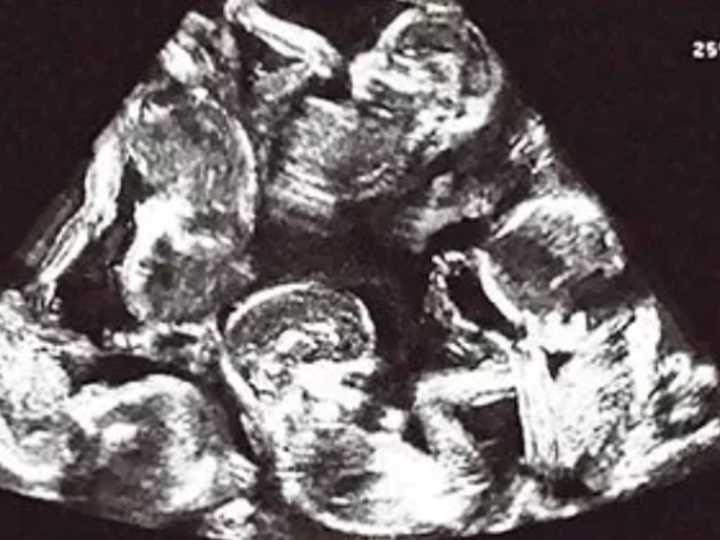

En un caso insólito que asombró a los médicos, una mujer egipcia se sorprendió durante unc ontrol rutinario de embarazo al descubrir que lleva nueve fetos en su útero a la vez, en un caso considerado uno de los más raros de la historia clínica.

Para averiguar la razón de esto, el doctor Wael Al-Banna, consultor en obstetricia y ginecología, reveló a Al-Arabiya y Al-Hadath que es uno de los casos médicos más raros registrados, dado que combina múltiples factores, el más importante de los cuales es la estimulación de los ovarios sin un seguimiento médico cuidadoso , lo que condujo a un embarazo con nueve fetos a la vez.